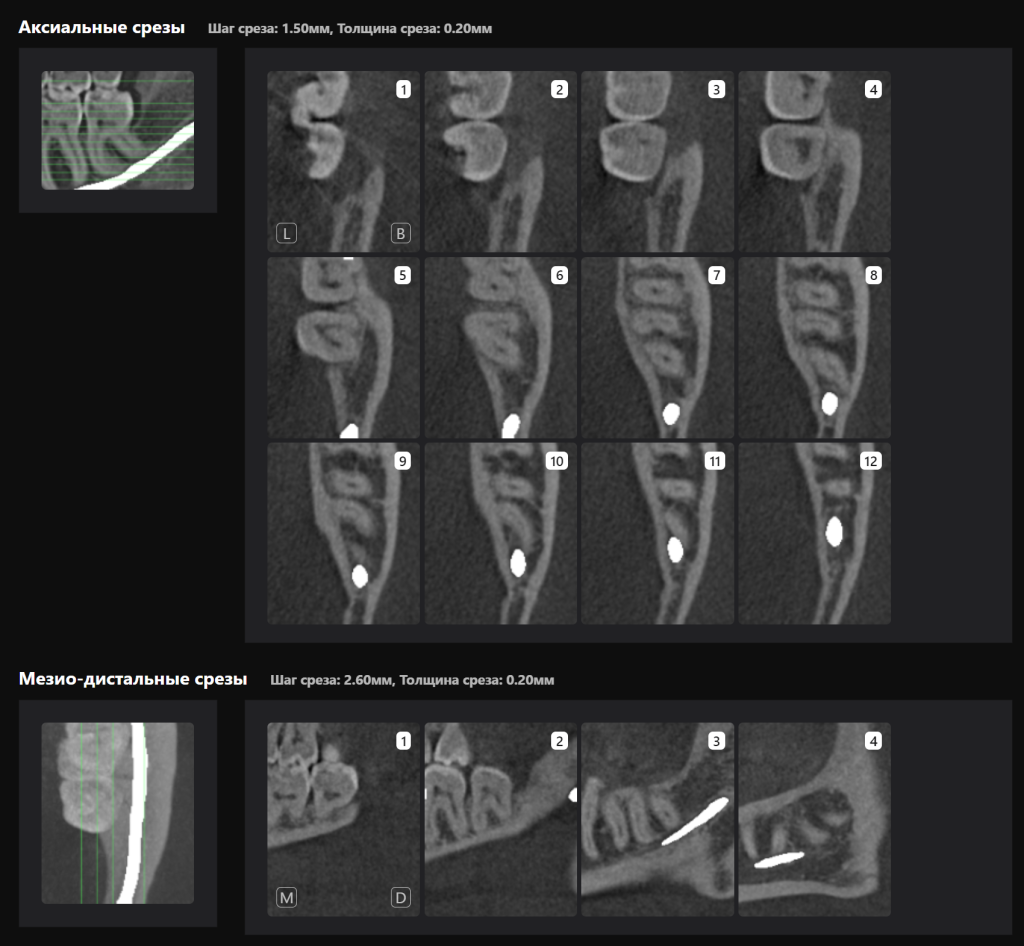

«Отчет по третьим молярам», созданный ИИ Diagnocat — это инструмент, который проводит точный трейсинг нижнечелюстного канала

И выстраивает оптимальную визуализацию в трех плоскостях и помогает врачу оценить расстояние до нижнечелюстного канала